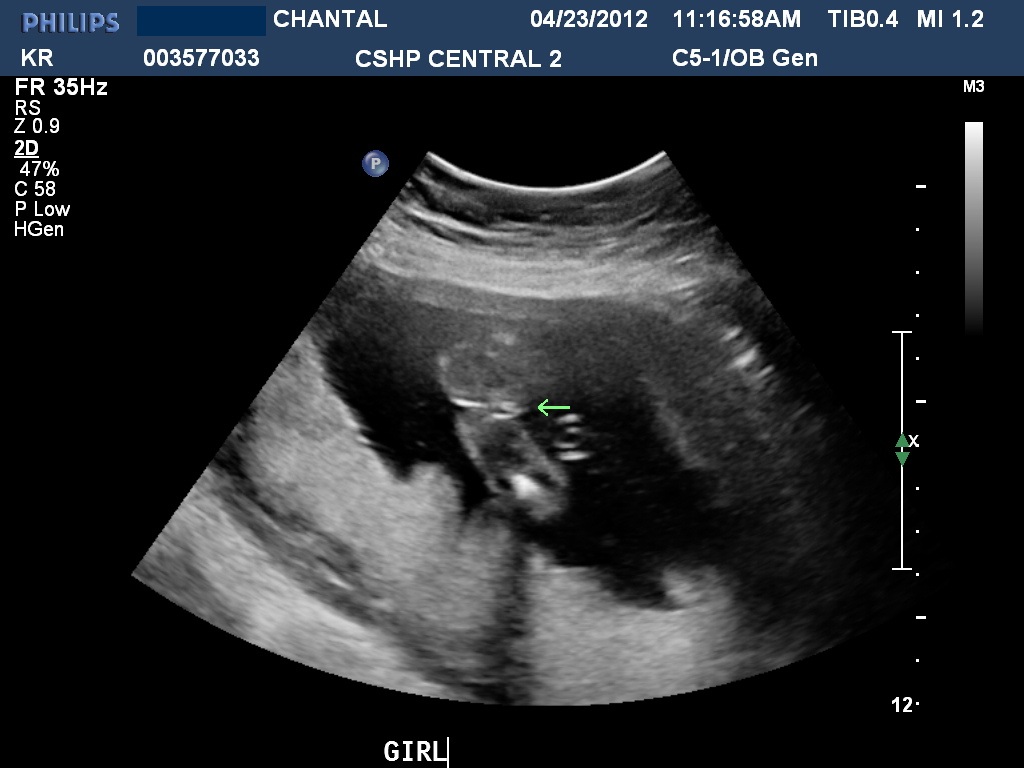

So I had my anatomy ultrasound this week and IT'S A GIRL!! So I definitely believe the skull theory now!

ANATOMY SCAN

Attachment 2237Attachment 2238